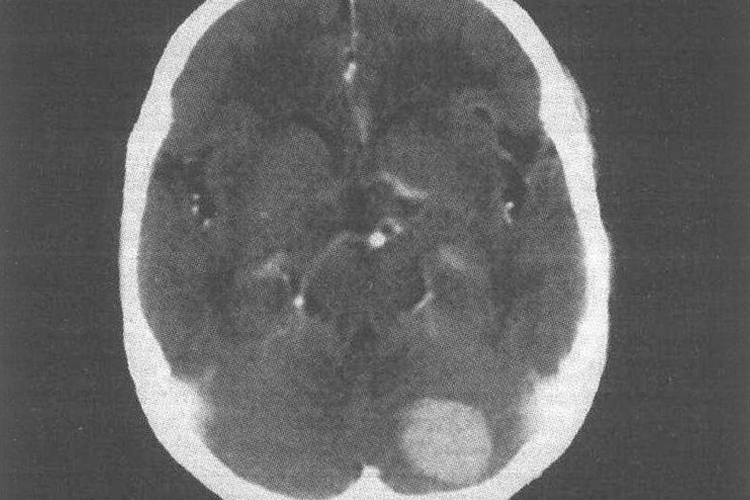

脑膜瘤

CT平扫肿块呈等或略高密度,常见斑点状钙化,多以广基底与硬膜相连,类圆形,边界清楚,瘤周水肿轻或无,静脉或静脉窦受压时可出现中度或重度水肿。颅板侵犯引起骨质增生或破坏。增强扫描呈均匀性显著强化。